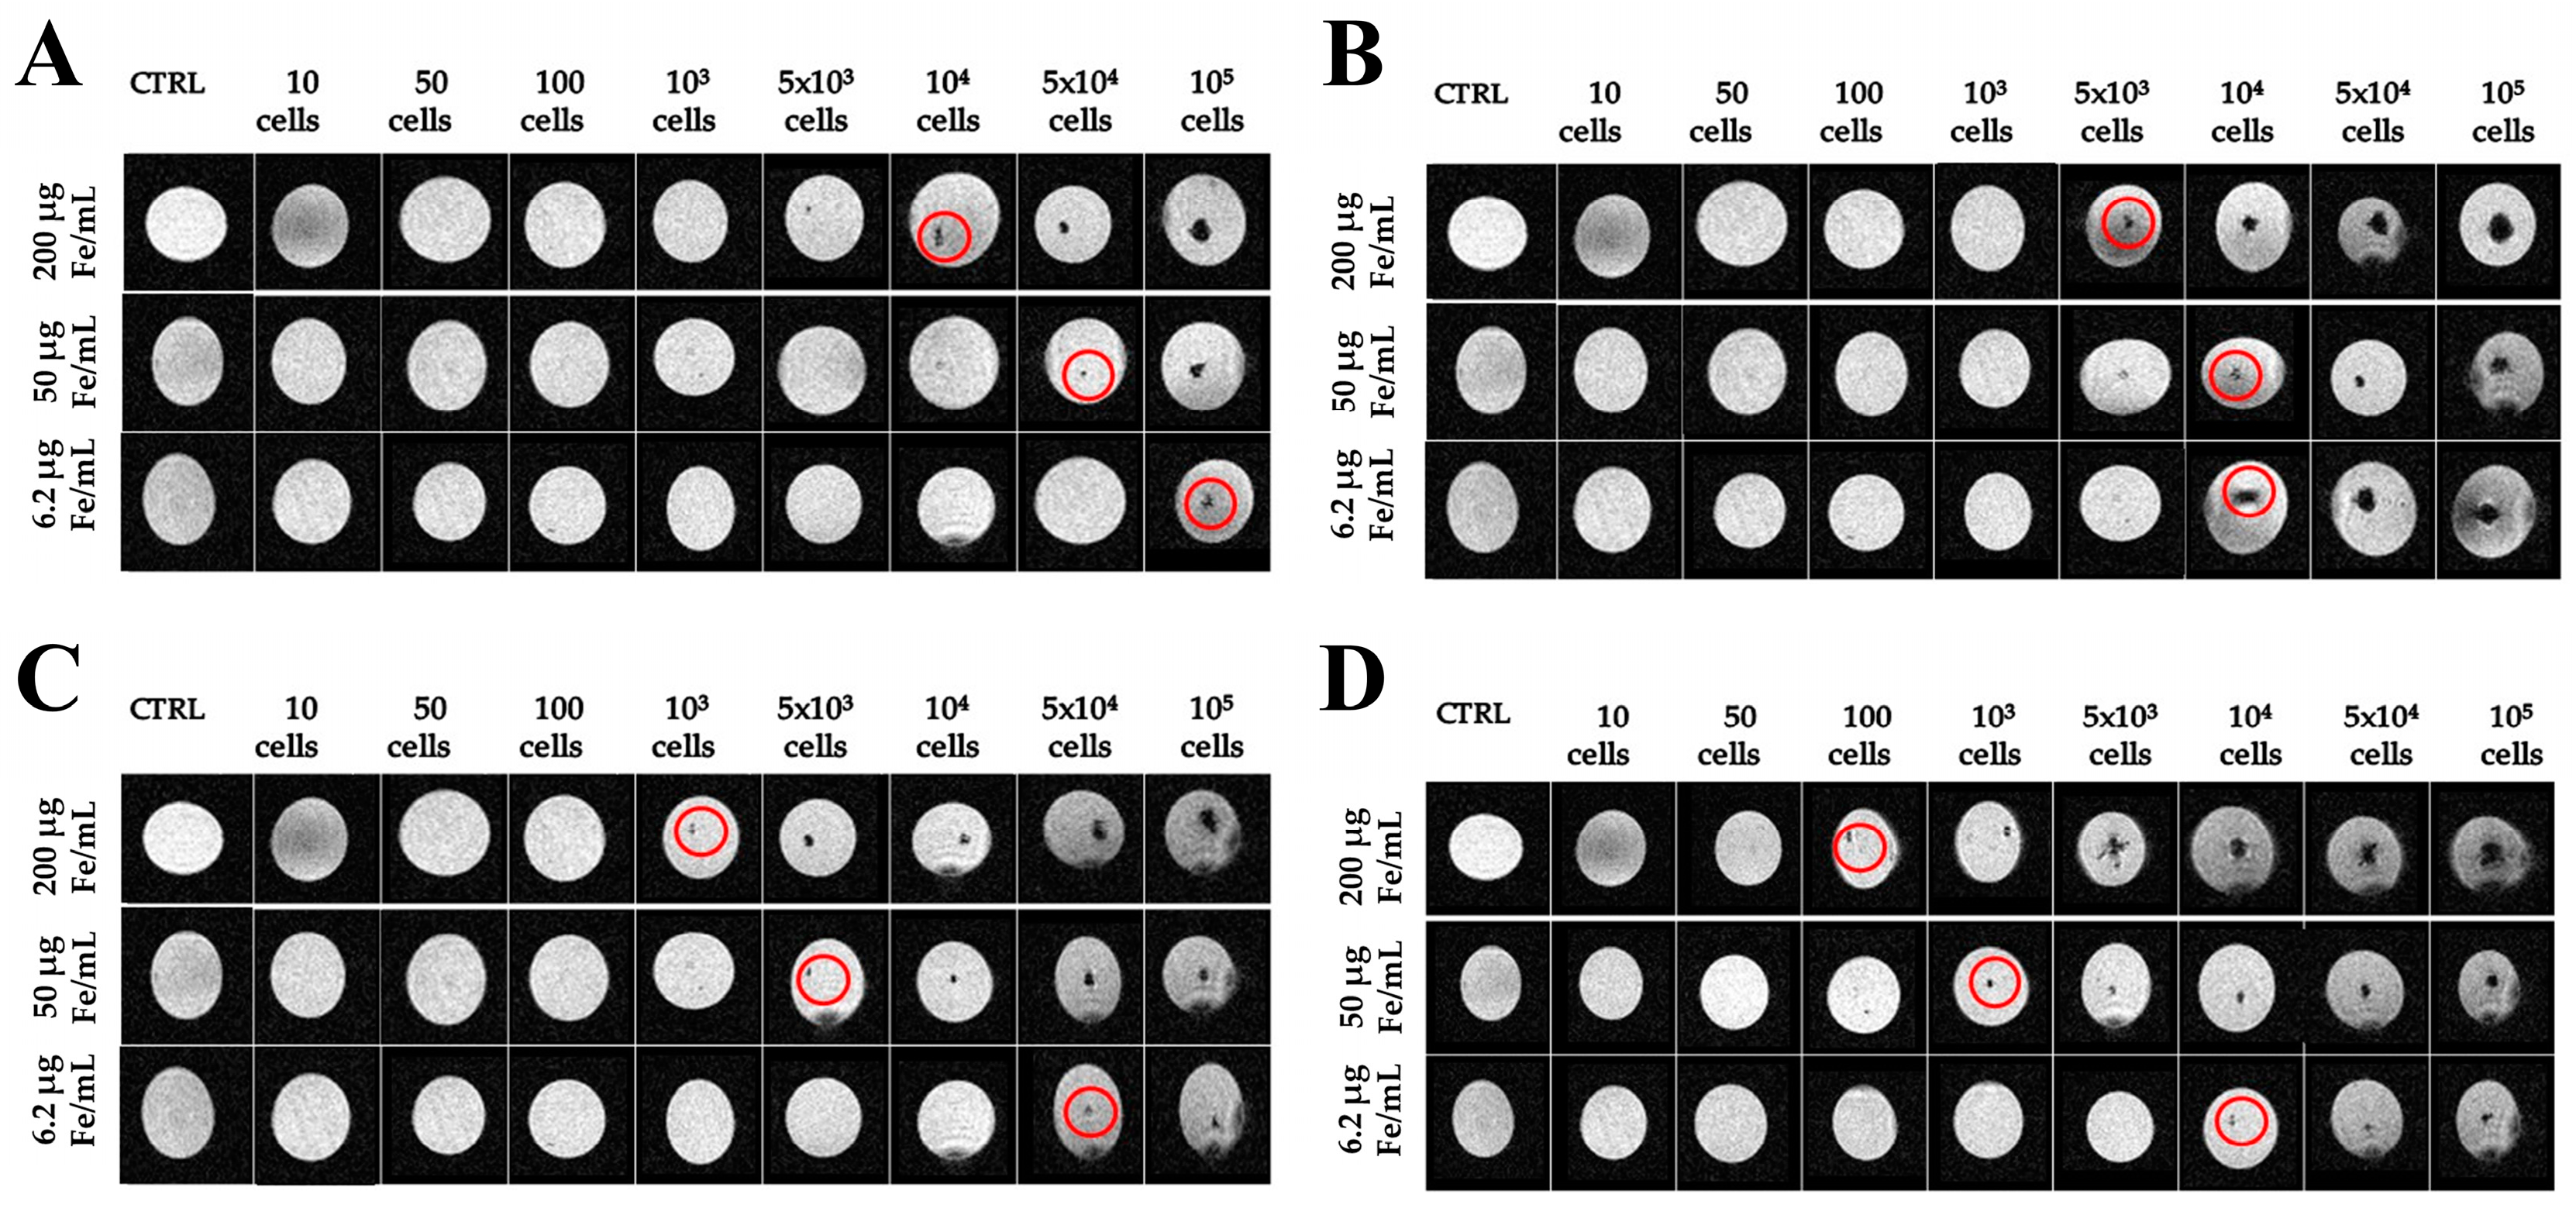

2.3. Imaging with Magnetic Resonance

4.3. Magnetic Resonance Imaging